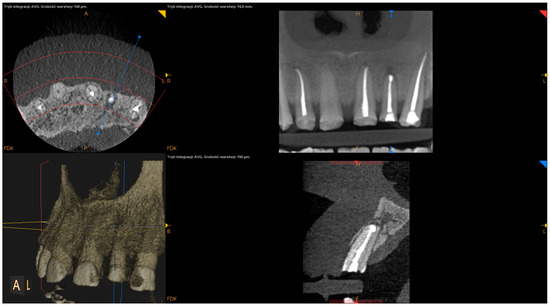

- The status of radiographic healing (rated in all sections, according to modified PENN 3D criteria [28]) was classified as complete healing (Figure 1), incomplete healing (Figure 2), uncertain healing (Figure 3), or unsatisfactory healing (Figure 4).

Figure 2. CBCT image (CS 8100 3D Carestream Dentalⓡ) example of incomplete healing based on PENN 3D criteria. Non-English annotations present software technicalities (AVG integration mode and layer thickness).